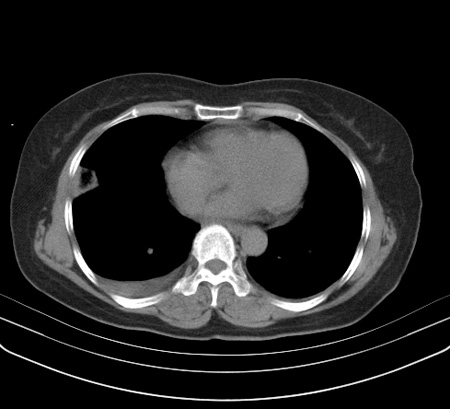

以下是引用余辉在2009-2-19 20:10:00的发言:[br]多考虑急性感染性病变,右中叶尚可见多枚小斑片状影,多为化脓性肺炎,双侧胸腔积液

以下是引用随光逐影在2009-2-19 20:33:00的发言:[br]1)考虑右肺炎症;建议抗炎治疗后复查。2)双侧胸腔积液(以右侧为甚)。

以下是引用花凤凰在2009-2-19 20:46:00的发言:[br]病人有发热,胸痛急性起病,主要病变位于右肺中叶外侧段,呈楔行改变,位于外带胸膜下,考虑为肺梗塞可能!!!!!!!!!!!!!!!!!!!!!!!!!!!!!!!!!!!